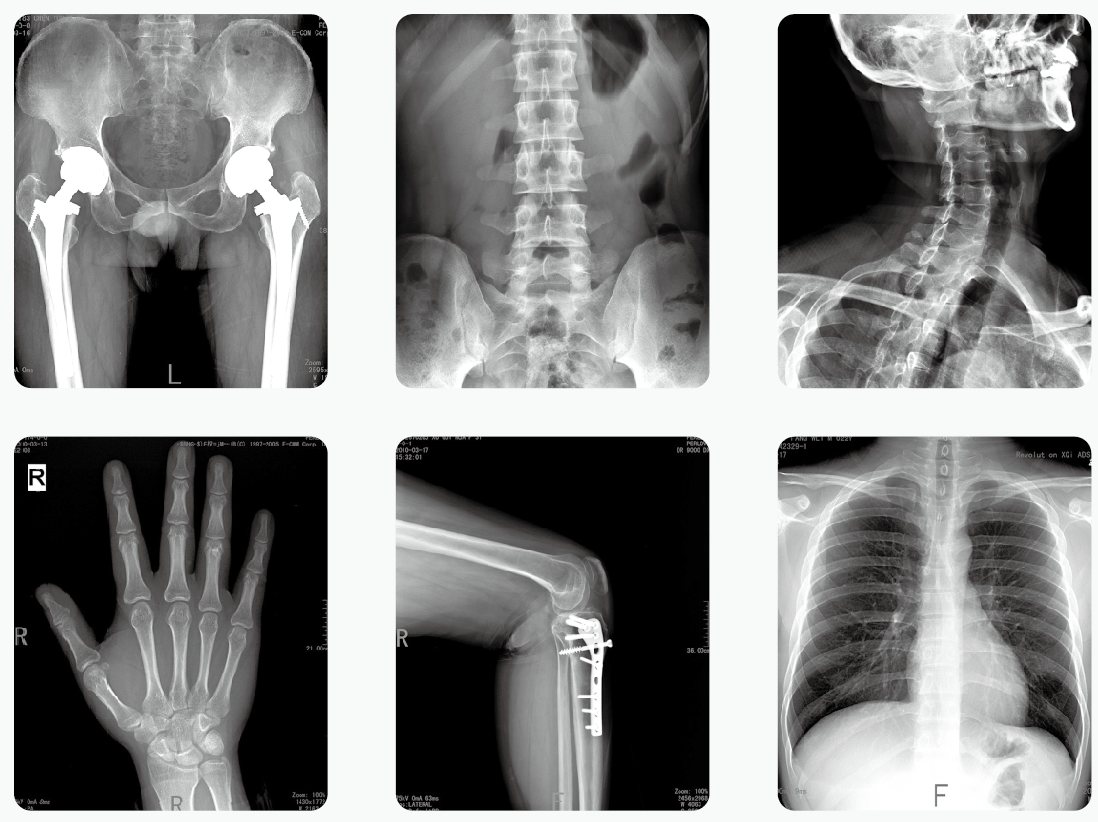

放射性醫(yī)學檢查:CT、DR會致癌嗎

CT、DR等放射性醫(yī)學檢查會危害健康的說法一直存在,這讓很多有所耳聞但不明真相的群眾對這類檢查很抵觸。事實上,放射性的檢查的確會有輻射,但是作為必要的醫(yī)療手段,醫(yī)療器械的輻射劑量是固定的,且遵循檢查原則偶爾進行一兩次這樣的檢查并不會對健康造成顯著影響。

放射性醫(yī)學檢查——DR

做一次CT,致癌的幾率有多大?

從動物實驗來看,除非暴露在長時間、大劑量的照射,否則,一般出現(xiàn)癌變、發(fā)生骨髓抑制的概率很低很低。

那怎么解釋居里夫人死于再生障礙性貧血(骨髓抑制)呢?

那是因為她整天跟放射性物質(zhì)打交道,長期、大量地接觸放射性物質(zhì),相當于時時刻刻在照CT。

其實CT是不會使人體產(chǎn)生癌癥的,有些人之所以會認為CT會導致癌癥,就是因為CT的輻射,實際上CT的輻射是非常小的,可以忽略不計。

做一次CTDR檢查對人體的致癌概率僅僅只有萬分之一,只要自己并不是經(jīng)常性的做這種檢查的話,就不會有致癌的可能性,即使是經(jīng)常做,醫(yī)生和護士也會給檢查者做好及時的防護工作,不會導致癌癥的產(chǎn)生。

人們之所以會如此害怕CT,就是因為大部分的人都以訛傳訛,使得有些人認為CT是一項非常麻煩,而且對身體有害處的檢查。如果說自己本身就有癌癥的話,做CT手術(shù)更是非常有必要的,只有通過CT的檢查,才能夠知道自己的癌細胞到底有沒有擴散,也能夠知道身體的各項機能到底是否正常。

其實人體的檢查項目是有很多的,每一種項目都有自己的獨有特色,也有一定的功效,如果說忽略哪一項檢查不做的話,可能其他器官的病變就不會被發(fā)現(xiàn),CTDR是一項比較重要的檢查項目,是應(yīng)該要做的。